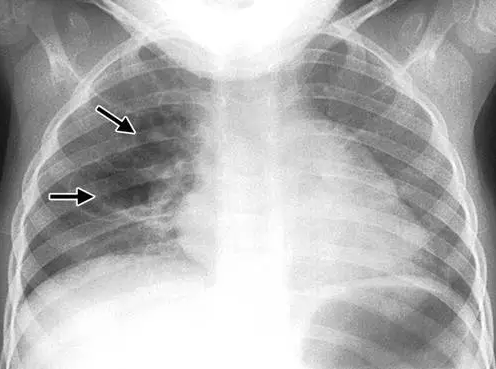

胸片和CT表现

肺气囊表现为肺内类圆形的,薄壁的含气腔(图1)。

图1 胸部X线片显示肺气囊(箭头)